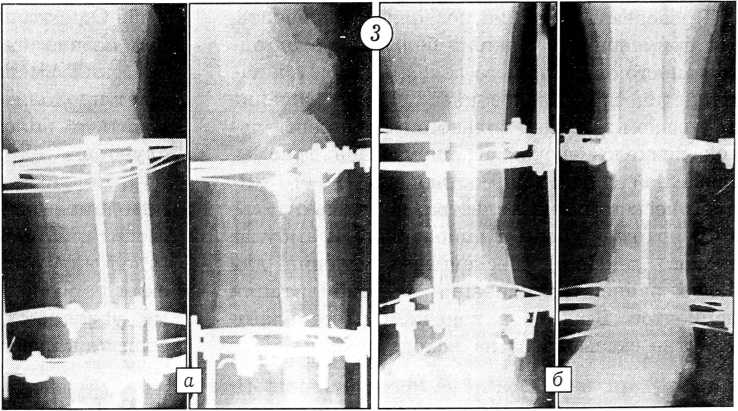

В дальнейшем осуществлялась дозированная дистракция в зонах кортикотомии (рис. 3).

Рис. 3. Тот же больной. Рентгенограммы левой голени в процессе компенсации укорочения: а — верхняя треть, б — нижняя треть.